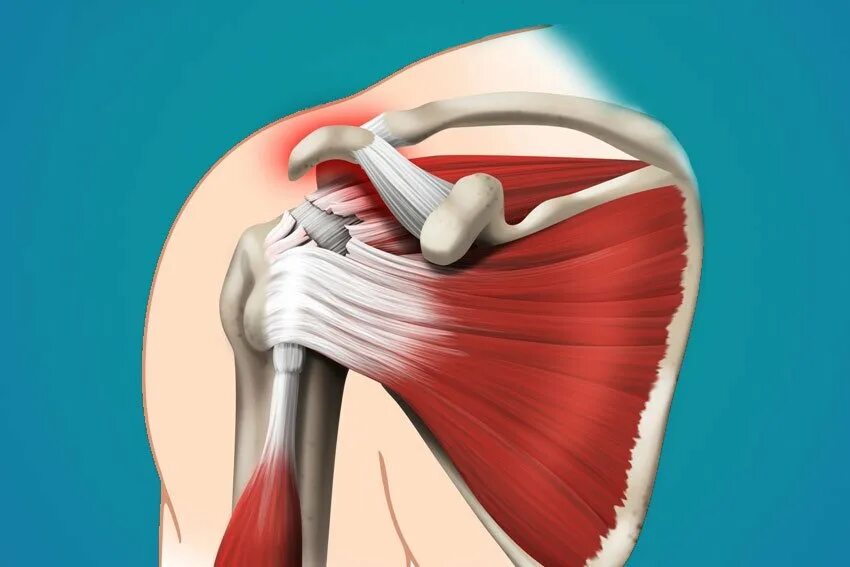

Разрыв длинных сухожилий